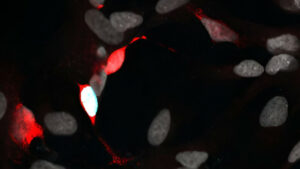

Un grupo de investigadores de la Universidad de Washington (EE.UU.) demostró que las células de la retina humana tienen la capacidad